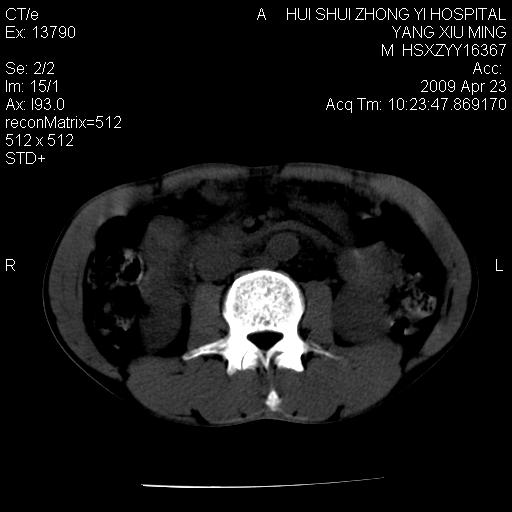

上腹部疼痛一月,呕吐10天,发现左侧颈部包快10天 胸部cr片未见明显异常。

腹膜后淋巴结增大,转移、淋巴瘤?胰腺增大,胰腺炎?占位?颈部考虑增大淋巴结。建议腹部增强扫描。

缺少强化资料,暂考虑胰腺癌广泛转移.

连最基本的ct值都没有测        腹部的窗宽窗位太大了     影响诊断

黑!广泛淋巴结肿大不符合胰腺癌转移。胰腺周围淋巴结肿大致使胰腺看起来大。考虑淋巴瘤可能大。

颈部及腹膜后淋巴瘤可能性大